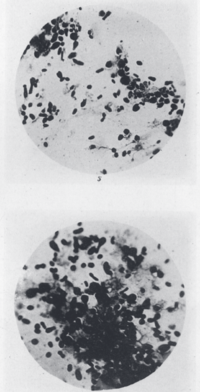

The British colonial government in India pressed medical researcher Waldemar Haffkine to develop a plague vaccine. After three months of persistent work with a limited staff, a form for human trials was ready. On January 10, 1897, Haffkine tested it on himself. After the initial test was reported to the authorities, volunteers at the Byculla jail were used in a control test. All inoculated prisoners survived the epidemics, while seven inmates of the control group died. By the turn of the century, the number of inoculees in India alone reached four million. Haffkine was appointed the Director of the Plague Laboratory, now called the Haffkine Institute, in Bombay.[59]